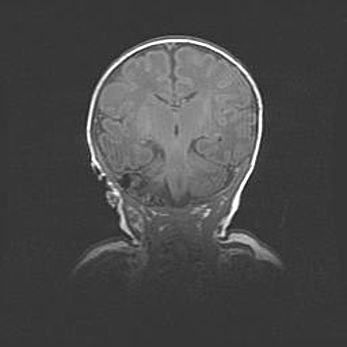

Аномалия Денди-Уокера. Признаки гипоплазии мозолистого тела.

Возраст: 5 месяцев 3 дня

Вес: 5550 г

Пол: мужской

Окружность головы: 39 см

Срок гестации: 40 недель

Аномалия Денди-Уокера – это порок развития головного мозга, для которого характерна триада симптомов: гипотрофия или аплазия червя мозжечка и/или полушарий мозжечка, расширение четвёртого желудочка с формированием ликворной кисты задней черепной ямки, гипертензионная гидроцефалия различной степени.

Гипоплазия мозолистого тела относится к дефектам внутриутробного этапа развития мозговой ткани, возникающим в процессе закладки структур головного мозга, что происходит на начальных этапах развития эмбриона.